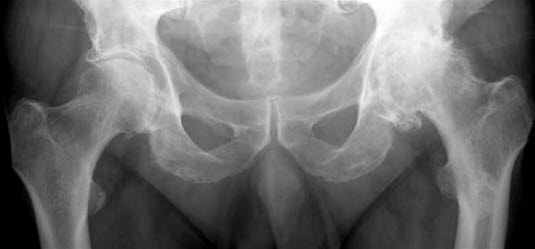

Betydelig mer artroseforandringer i venstre hofteledd.Hofteleddet består av hofteskåla, som er en del av bekkenbeinet, og lårbeinets hoftekule. Både hofteskålen og hoftekulen er "kledd" med glatt brusk som sikrer at bevegelser foregår med minst mulig motstand.

Hofteleddet er det leddet i kroppen hvor artrose forekommer hyppigst. Hos eldre ser man ofte slitasjeforandringer på røntgen, men bare en liten andel av disse pasientene har symptomer. Så artrose påvist på røntgen, er ikke ensbetydende med store plager. 90 prosent av pasientene over 65 år som klager over hoftesmerter, har artrose i hofteleddet. I 2019 ble det satt inn over 9879 hofteproteser i Norge, og det ble utført 101 reoperasjoner og 1384 revisjoner.

Startsmerter ved gange som blir bedre, for så å forverres ved fortsatt gange, er svært typisk for diagnosen. Ved undersøkelse av hoften finner legen at bevegeligheten er nedsatt, særlig ved rotasjon innover og utover. Blodprøver har ingen betydning for å stille diagnosen. Røntgenbilder av hoften viser karakteristiske forandringer og bekrefter diagnosen.